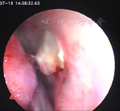

术后情况:患者术后照片见图3。1周拆除鼻中隔缝线,鼻中隔穿孔愈合(图4),术后25 d见图5。鼻底部供区2个月后瘢痕上皮化完成,原有鼻塞、鼻干、涕中带血消失,疗效明显。1年后复诊鼻中隔愈合良好,鼻部症状明显改善。